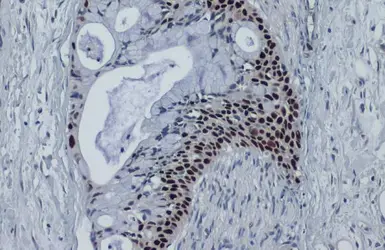

Anti-p53 antibody [DO1] used in IHC (Paraffin sections) (IHC-P). GTX70214

GTX70214 IHC-P Image

p53 antibody [DO1] detects p53 protein at cytoplasm and nucleus by immunohistochemical analysis.

Sample: Paraffin-embedded human colon cancer.

p53 stained by p53 antibody [DO1] (GTX70214) diluted at 1:100.

Antigen Retrieval: Citrate buffer, pH 6.0, 15 min

6 / 14